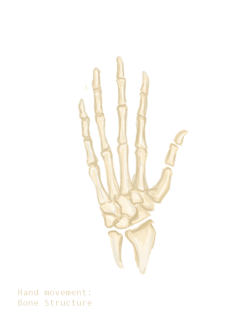

العظام

يد الإنسان مكونة من 27 عظاما :

- الرسغ ويضم 8 عظام تشكل صفين بكل واحد 4 عظام.

- مشط اليد وهو مجموعة العظام التي تشكل راحة اليد، وعددها 5.

- السلاميات هي مجموعة عظام أصابع اليد وعددها 14.